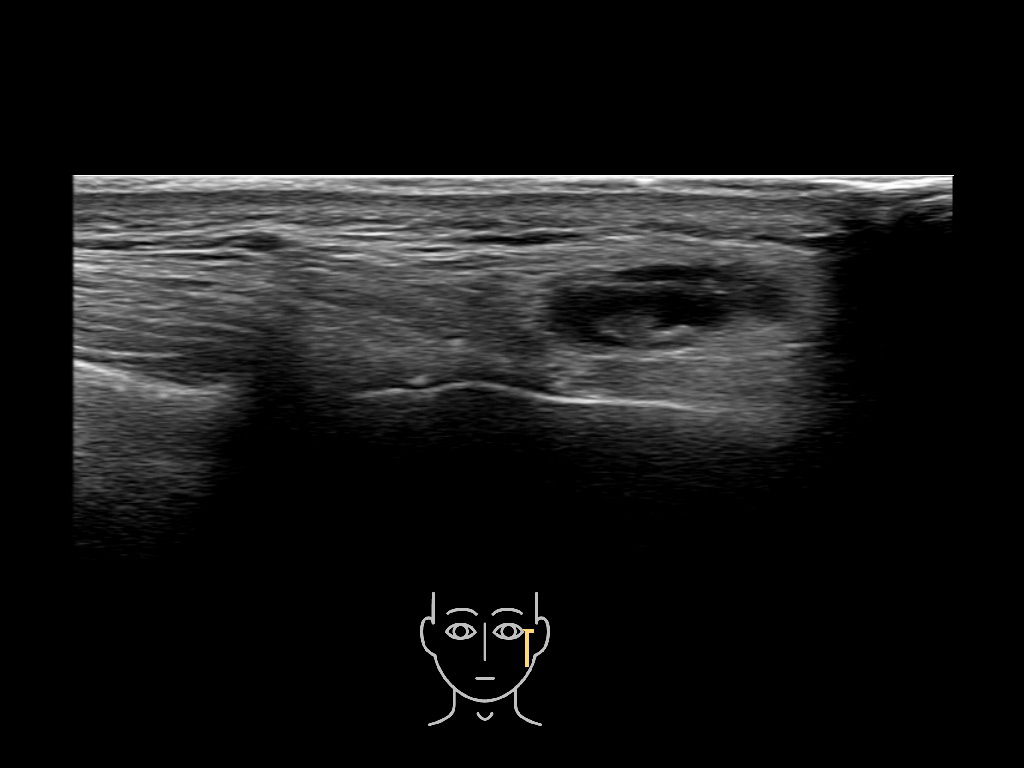

Filler injections in the parotid gland may go unnoticed, however, inflammatory reactions and abscesses may occur. Hypervascularity can be seen with color doppler. Filler deposits are supposed to be injected into the superficial fatty layer . The space to inject into this layer may be limited. Routinely we measure a width of 2-4 millimeters with sometimes subcutaneous layers being less than one millimeter thick.

Study the first image to recognize the different layers. If you are sure about the layers, swipe to the second image to view the answer (if applicable).